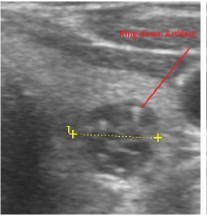

In our study many patients were found to have nodules look very much like PT adenoma, Figure 7 below. At least, 4 patients were subsequently confirmed to have parathyroid adenomas, Figure 8 and 2 patients underwent surgery

Despite the fact that nodular pathology was found to be very prevalent among our study population, it has been found difficult to differentiate between thyroid and parathyroid pathology using ultrasound alone. However, some characteristics of the parathyroid glands might suggest parathyroid pathology in the context of the clinical picture of secondary or tertiary hyperparathyroidism which is very prevalent in ESKD patients’ populations.

Figure 7.Thyroid nodule suspicious for Parathyroid adenoma due to its location

Figure 8.Nodule that proven to be a parathyroid adenoma, volume =5265 mm3